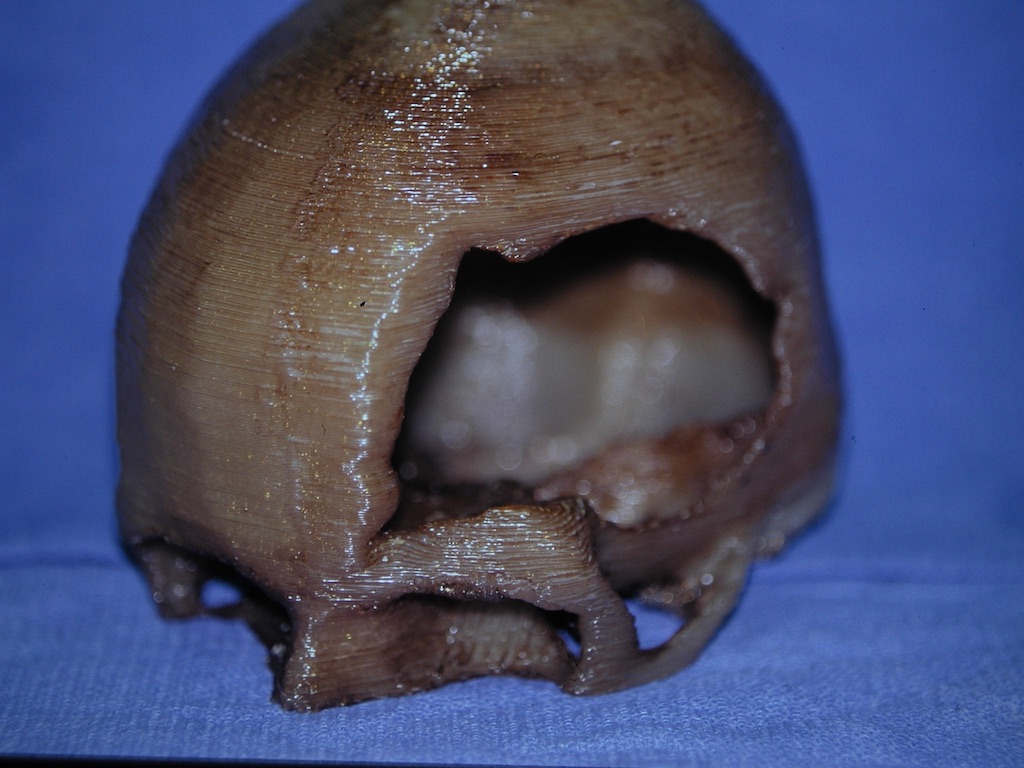

Patient 28

Desire for rounder shape to the top of the head from a congenital parasagittal deficiency skull shape.

Custom skull implant designed to fill in the parasagittal deficiencies.

Desire for rounder shape to the top of the head from a congenital parasagittal deficiency skull shape.

Custom skull implant designed to fill in the parasagittal deficiencies.